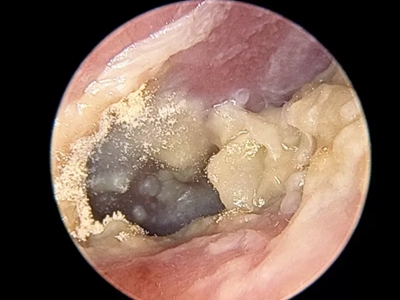

外耳道

肉赘 · 脱屑

霉菌性外耳道炎外耳道有白粉末里边有肉赘图

霉菌性外耳道炎患者外耳道边缘有大量的白色鳞屑,融合呈团片状,形状不规则,境界清楚,同时在外耳道深处有乳头状肉赘,外观类似小葡萄。